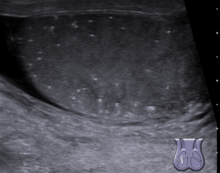

Testicular microlithiasis is an unusual condition diagnosed on testicular ultrasound. It is found in between 1.5 to 5% of normal males, and may be found in up to 20% of individuals with subfertility. It is an asymptomatic, non-progressive disease. The cause is unknown, but this condition has been associated with testicular cancer in a small group of individuals, cryptorchidism, mumps, infertility and intraepithelial germ cell neoplasia. Classic testicular microlithiasis is defined as five or more echogenic foci per view in either or both testes, and limited testicular microlithiasis defined as one or more echogenic foci that do not satisfy the criteria for classic testicular microlithiasis. In 80% of cases, both testicles are affected.